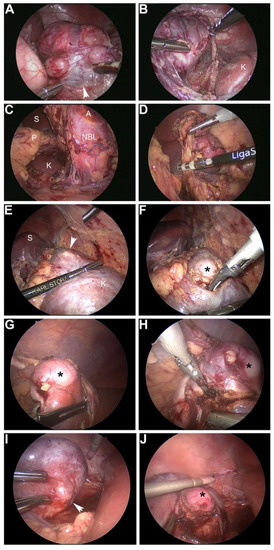

- Phelps, H.M.; Ayers, G.D.; Ndolo, J.M.; Dietrich, H.L.; Watson, K.D.; Hilmes, M.A.; Lovvorn, H.N., 3rd. Maintaining oncologic integrity with minimally invasive resection of pediatric embryonal tumors. Surgery 2018, 164, 333–343. [Google Scholar] [CrossRef] [PubMed]

| Phelps 2018 [14] | 17 laparoscopy | 17 resection 13 NBL 3 WT 1 RMS | 0 | No acute complications |

| 8 thoracoscopy | 8 resection 8 NBL | 0 | No acute complications | |